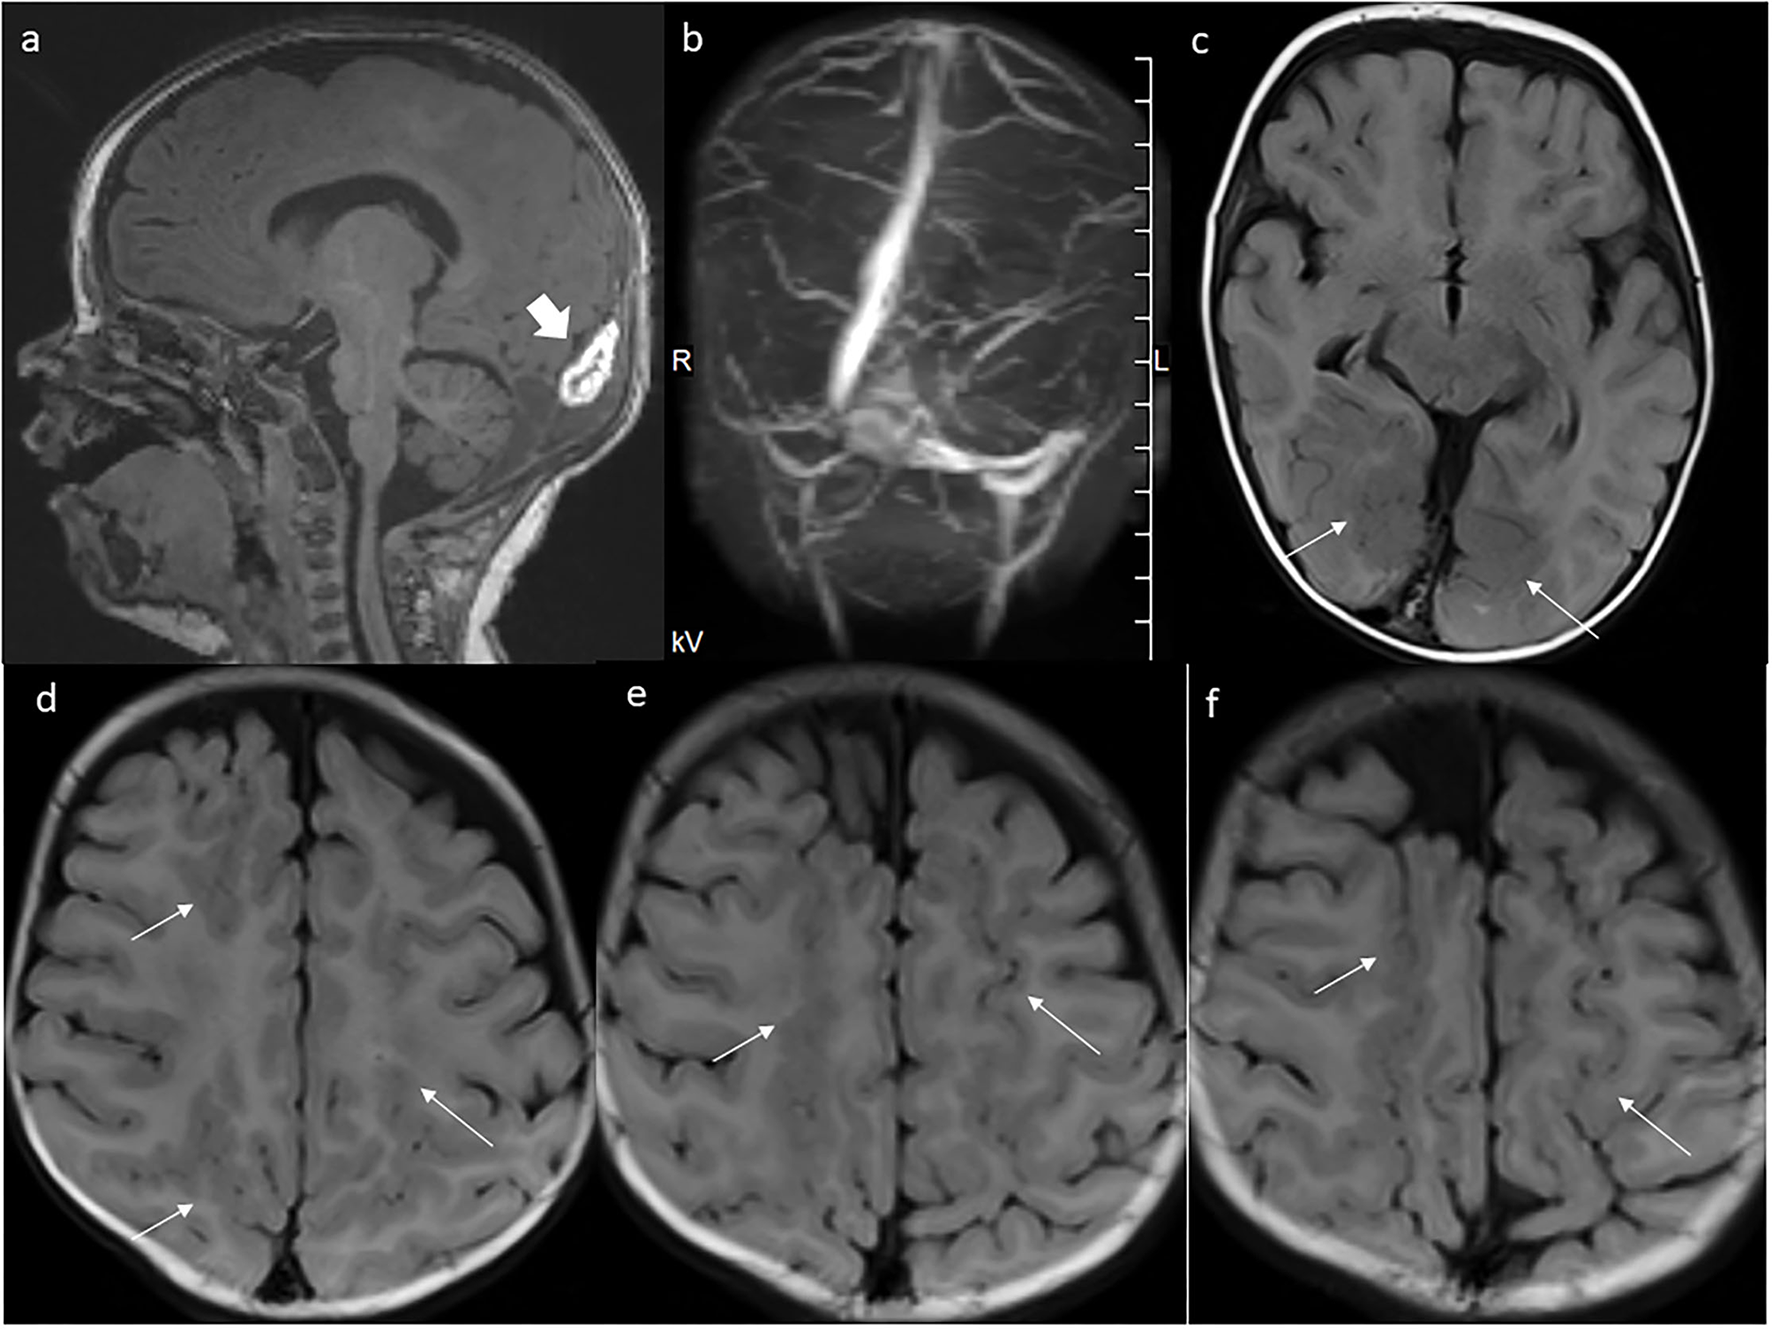

Figure 4

MRI at the age of 5 months. (a) Further thinning of the mass. (b) Patent dural venous sinuses in MR venography. (c–f) The extent of polymicrogyria in the parasagittal parts of the occipital, parietal, and frontal lobes is even better seen now in axial FLAIR images.

In the 5th month of life, a control brain MRI showed a slightly smaller mass within the torcular herophili (23 × 6 × 9 mm; Figure 4a), with smaller hemosiderin deposits in SWI sequence. The MR venography showed the flow in all dural sinuses (Figure 4b). The malformation of cortical development was prominently visualized in FLAIR sequence (Figures 4c–f).